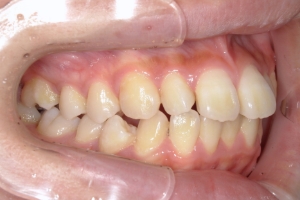

PROCESS

半年

下の前歯が上あごの歯ぐきに当たるほど噛み合わせが深く、そのことが原因で上顎歯列の正中にすき間(正中離開)が生じていました。部分矯正ですき間を無理やり閉じても、噛み合わせが深いままでは治療後の再発リスクが高くなります。そのため全体矯正で奥歯の噛み合わせを整え、噛み合わせを浅くしつつ前歯を並べました。正中離開は戻りやすい傾向があるので、再発を防ぐため固定式リテーナーを推奨しています。